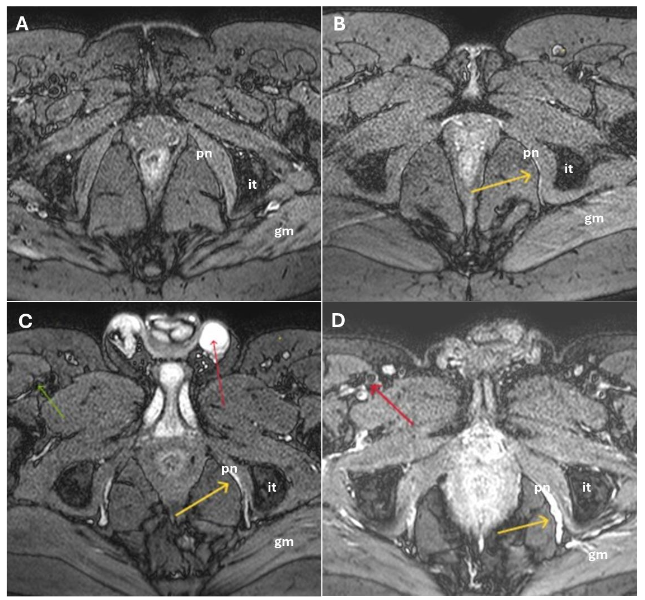

In cases of injury, the pudendal nerve appeared as a hyperintense linear structure on DP SPAIR double IR BB sequences. Coronal oblique views were optimal for visualizing the nerve’s exit and re-entry near the ischial spine, while axial oblique views best depicted its course through Alcock’s canal.

A 0-3 point brightness visual scale (B-scale) was developed to grade pudendal nerve injury within Alcock’s canal by comparing its signal intensity on axial DP SPAIR double IR BB images to that of static intravescical fluid, where 0 = no hyperintensity (no injury); 1 = barely visible hyperintensity (mild injury); 2 = clearly visible hyperintensity (moderate injury); and 3 = maximum intensity, equal to that of tissues containing static fluid (severe injury).

MR FINDINGS

MR neurography was successfully performed in all 100 patients using the described 1.5T protocol. Image quality was deemed sufficient for diagnostic interpretation in 96% of cases by both Observer 1 and Observer 2. The pudendal nerve was consistently visualized in cases of damage, appearing as a hyperintense linear structure on DP SPAIR BB images along its course from the sacral foramina to its terminal branches within Alcock’s canal, without the need for contrast administration.

Signal abnormalities were most frequently observed at the level of the ischial spine and Alcock’s canal, consistent with known anatomical entrapment sites. Additional findings included architectural distortion, nerve thickening, and obliteration of perineural fat planes features indicative of chronic neuropathic changes.